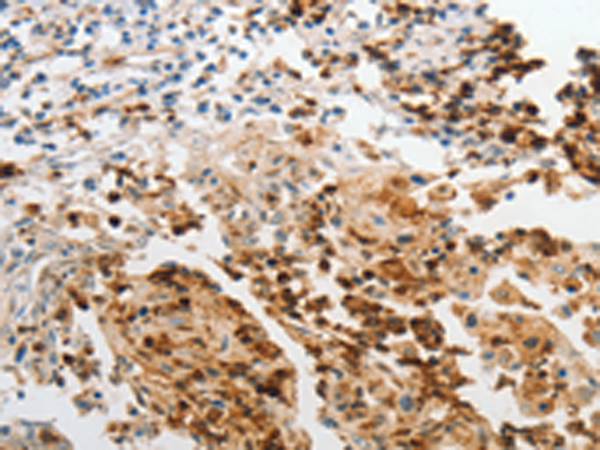

分类: 科研抗体货号: P11262别名: ARG; ARP; DNB1; ATN1L应用: IHC反应种属: Human, Mouse, Rat